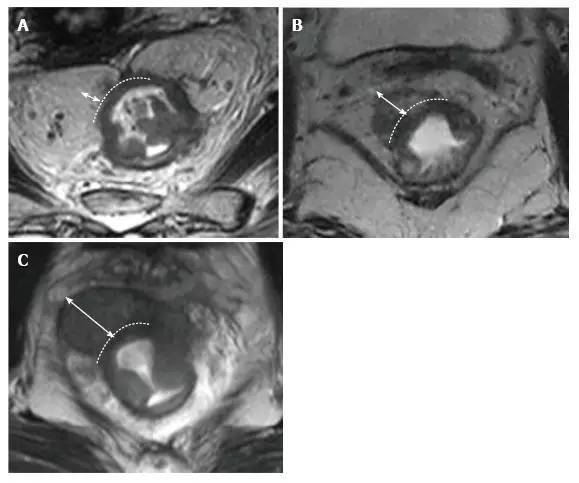

3.N 分期

CRT 后淋巴结大小用于重新分期更可靠,放疗导致的正常淋巴结形态学变化使得转移淋巴结与正常淋巴结很难采用形态学和 DWI 相区分,经常导致淋巴结过度分期(图 24 和图 25)。

图片

图 24. DWI 对直肠癌放化疗后 ypT0N0 直肠系膜淋巴结评估假阳性。A. T2 加权轴位磁共振图像显示放化疗后结节大小明显减少,与阴性淋巴结(箭头)相符;B. DWI 图像,直肠周围淋巴结治疗后高弥散信号,与阳性淋巴结(箭头)相符。

图 25. DWI 成像,直肠癌放化疗后 ypT0N0 阳性直肠系膜淋巴结。A. T2 加权轴位图像显示淋巴结大小明显减少,与完全反应相符;B. 残余的纤维化淋巴结呈现高弥散信号强度,错误提示为转移性淋巴结(箭头)。